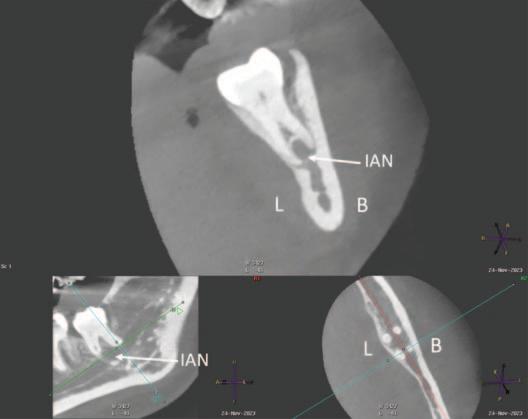

At the oral surgery consultation, the patient also noted a four-week history of intermittent discomfort in the LL8 region, described as throbbing pain with associated swelling of the gum, made worse by chewing and applying pressure to the tooth. This presentation was in keeping with recurrent pericoronitis. A cone-beam computed tomography (CBCT) scan was undertaken, which identified four roots of LL8 and associated loss of IAN canal cortication. The IAN pathway grooved the distobuccal root and passed between/penetrated the mesial roots (Figures 2 and 3).

FIGURE 2: Association of IAN with mesial roots (L = lingual, B = buccal, IAN = inferior alveolar nerve).

FIGURE 3: Association of IAN with distal roots (L = lingual, B = buccal, IAN = inferior alveolar nerve).